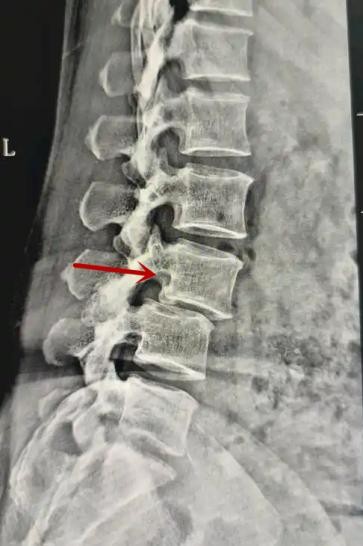

利器一:X線/DR

腰椎X線片作為最基礎(chǔ)的影像檢查手段,利于X線穿透人體組織后成像,以其快捷、直觀、價(jià)格低廉的特點(diǎn),X線檢查主要包括腰椎正側(cè)位、雙斜位以及過伸過屈位。主要用于觀察腰椎骨骼的情況,如椎體是否有骨折、骨質(zhì)增生程度、生理曲度的變化、椎體移位的情況等。然而,X線檢查也有它的局限性,無法判斷是骨折的新舊,對(duì)于椎體內(nèi)部結(jié)構(gòu)和周圍肌肉韌帶組織(如脊髓神經(jīng)、椎間盤、韌帶等)的顯示不佳,另外X線作為有輻射檢查,孕婦及嬰幼兒謹(jǐn)慎選擇。

箭頭提示腰1椎骨折

箭頭提示腰3椎體滑脫